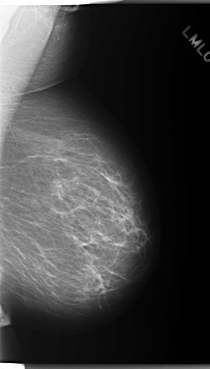

C_0147_1.RIGHT_MLO

C_0147_1.RIGHT_CC

RIGHT_MLO LINES 5832 PIXELS_PER_LINE 3664 BITS_PER_PIXEL 12 RESOLUTION 50 OVERLAY